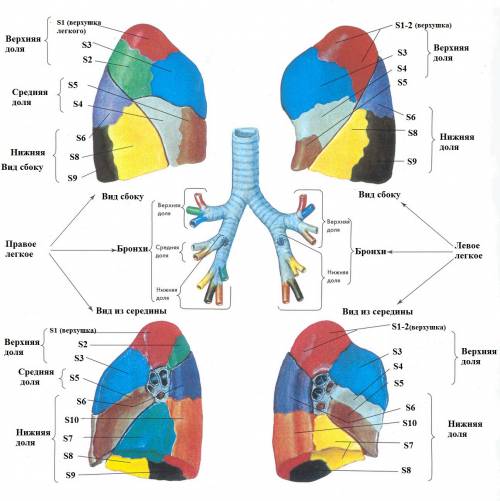

Анатомические изображения сегментов легких различных животных

Раздел: Другие животные